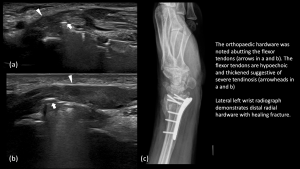

Fig 16: POST CTR SURGERY PALMAR CUTANEOUS BRANCH (PCB) NEUROMA AND FCR TENOSYNOVITIS FCR tenosynovitis with tendinopathy - Post Open Reduction Internal Fixation (ORIF)/Carpal Tunnel Release (CTR), median nerve neuroma/thickening at the wrist crease proximal to the carpal tunnel

Fig 17: POST ORIF/CTR MEDIAN NERVE NEUROMA/THICKENING AT WRIST CREASE PROXIMAL TO THE CARPAL TUNNEL

Fig 18: POST ORIF/CTR MEDIAN NERVE NEUROMA / THICKENING AT WRIST CREASE PROXIMAL TO THE CARPAL TUNNEL Post ORIF hardware abutment and flexor tendinosis - Post coronary artery bypass graft surgery (CABG), Median Nerve Neuropathy in Mid Forearm